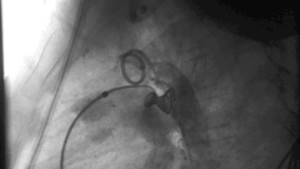

Пациентам с открытым артериальным протоком показана хирургическая операция. Лигирование сосуда проводится либо на открытой грудной клетке (более травматичная тактика лечения), либо с помощью специального катетера, который вводится в магистральные сосуды и позволяет установить внутри артериального протока специальный окклюдер Койла. Это наиболее распространенная минимально инвазивная техника. Результатом ее является полное перекрытие просвета Боталлова протока, предотвращение патологического сообщения между аортой и легочной артерией. Раскрытие грудной клетки при этом не требуется.